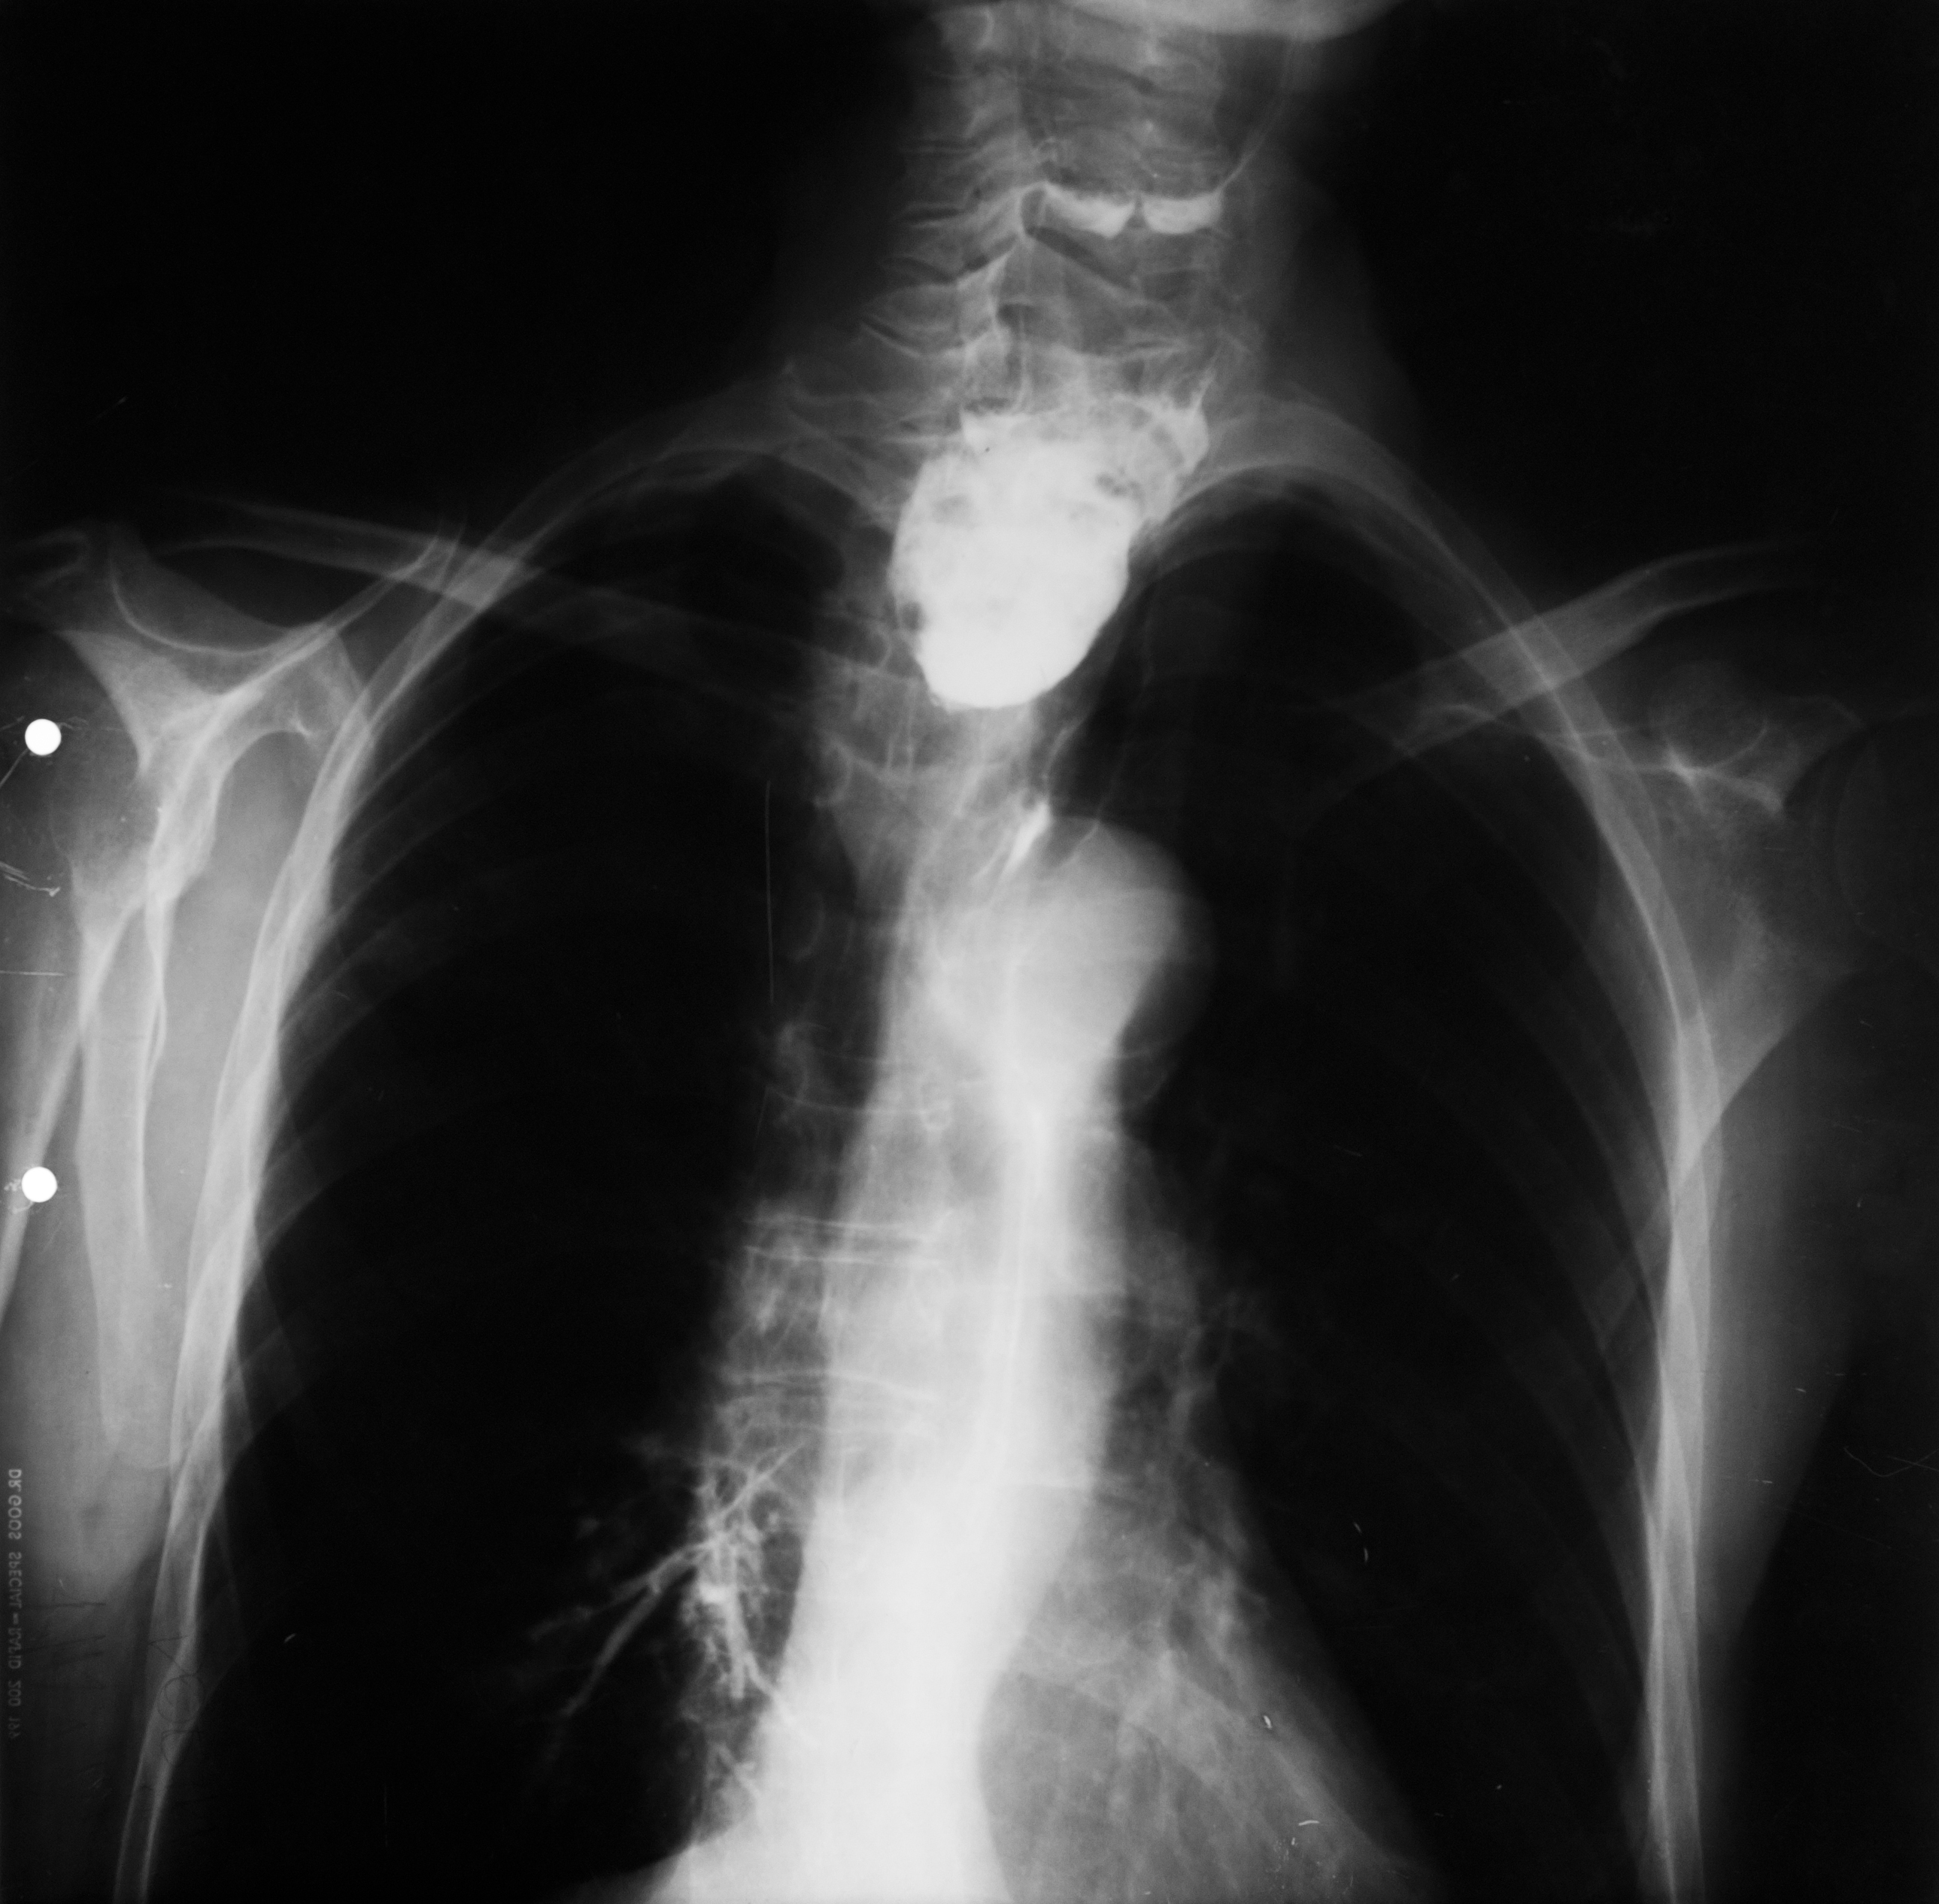

Rx toraco-mediastino-pleuro-pulmonară,incidența de față – vedem o imagine toracică normală (ITN) cu desen pulmonar,cu hil,fara nicio modificare patologică